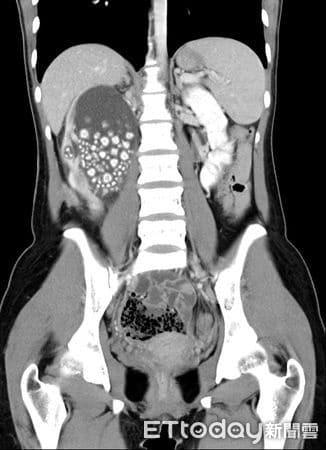

Μια 20χρονη γυναίκα, επισκέφθηκε το νοσοκομείο, νομίζοντας ότι έπασχε από απλό πυρετό και έντονους πόνους στη μέση. Αντί γι’ αυτό, οι γιατροί ανακάλυψαν πως το νεφρό της ήταν γεμάτο με περισσότερους από 300 πέτρες — τόσους πολλές, που ένας γιατρός το παρομοίασε με ταψιά γεμάτα μικρά ψωμάκια ατμού.

Η νεαρή γυναίκα άρχισε να νιώθει έντονη κόπωση, πυρετό και πόνους στη μέση. Οι γιατροί αρχικά υποψιάστηκαν λοίμωξη του ουροποιητικού ή φλεγμονή των νεφρών — καταστάσεις που αντιμετωπίζονται εύκολα. Όμως οι αξονικές και υπερηχογραφικές εξετάσεις αποκάλυψαν κάτι απίστευτο: το δεξί της νεφρό ήταν διογκωμένο και φραγμένο με εκατοντάδες πέτρες σαν μεγάλους κόκκους άμμου σχεδόν δύο εκατοστών.

Οι περισσότεροι ασθενείς έχουν έναν ή δύο πέτρες. Η νεαρή αυτή γυναίκα είχε εκατοντάδες, που συσσωρεύονταν επί χρόνια λόγω αφυδάτωσης, μέχρι που το σώμα της κατέρρευσε. Οι πέτρες είχαν μπλοκάρει το σύστημα διήθησης των νεφρών, προκαλώντας λοίμωξη και πυρετό.

H ακτινογραφία με τις πέτρες πάνω αριστερά